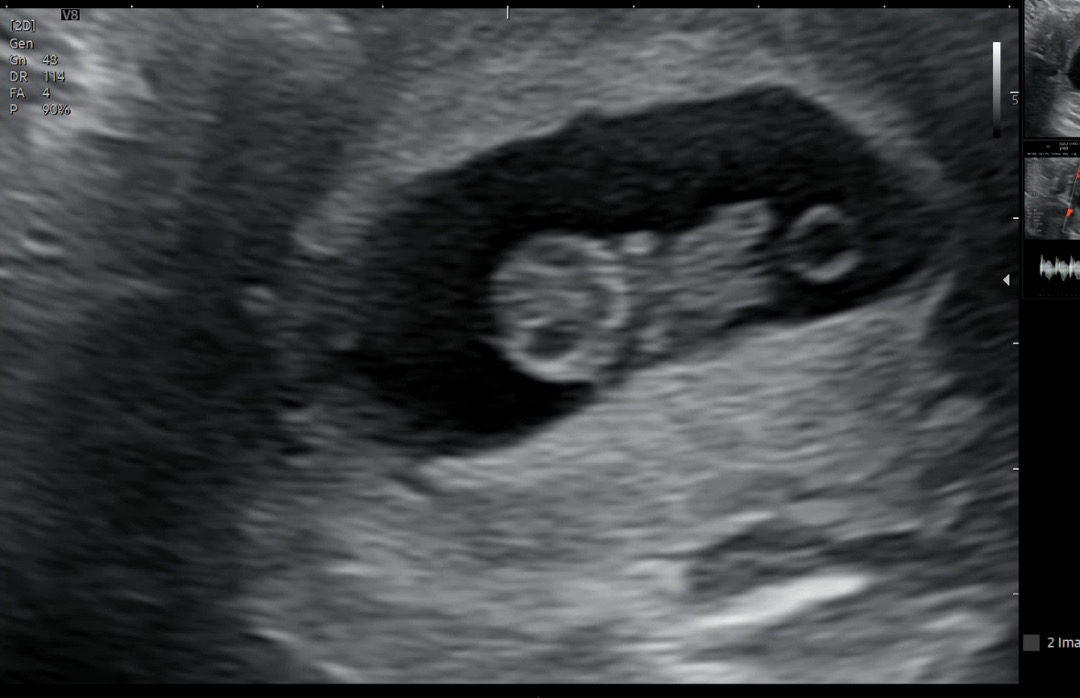

9주1일차 초음파

2주를 열심히 기다리고 정기검진날이라 아기보고왔어요.! 젤리곰이 되어서 꼬물거리는게 참신기하고 귀엽더라구요ㅎㅎ 7주차에 있던 피고임 없어져서 피도안나고 심박수랑 크기도 문제없이 잘 있는거보니 이제서야 좀 안심이 되네요ㅜㅜ 혹시나 하며 불안할때가 얼마나많았는지 두통과입덧으로 힘들지만 잘 이겨내봐야죠 다들 화이팅하자구요!!